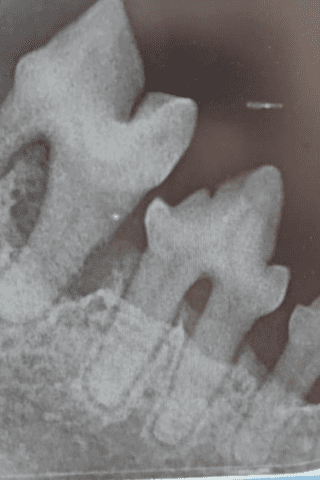

Parodontiittia kissan hampaissa.

Parodontiitti eli hampaan kiinnityskudoksen tulehdus on etenevä sairaus. Tutkimusten mukaan siitä kärsii jopa 85 % yli 6-vuotiaista kissoista. Sairaudelle voivat altistaa mm. lyttykyonoisuuden aiheuttama hampaiston ahtaus, diabetes mellitus, kissaviroosit sekä immuunokatotaudit, jotka heikentävät elimistön immuunivastetta ja johtavat epänormaaliin vasteeseen plakkibakteereille. Diagnoosi tehdään hammastarkastuksessa tutkimalla hampaat ja mittaamalla ientaskut, ja lisäksi otetaan röntgenkuvat. Hammastarkastuksessa jokainen hammas käydään yksitellen läpi eli kaikki kissan 32 hammasta tutkitaan. Kissoilla tavataan myös aggressiivista parodontiittia, joka alkaa nuorella iällä, joskus jopa alle 1-vuoden iässä. Lue ylempää juveniilista ientulehduksesta ja parodontiitista.

Pitkälle edenneitä parodontiittimuutoksia kissan hampaissa.